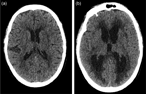

Anaplasic astrocytoma with exophytic growth in Sylvian fissure in a pediatric patient: a case report

José Raúl Guerra-Mora and others

Journal of Surgical Case Reports, Volume 2018, Issue 4, April 2018, rjy079, https://doi.org/10.1093/jscr/rjy079